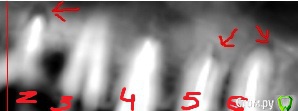

klemento Опубликовано 30 сентября, 2019 Поделиться Опубликовано 30 сентября, 2019 (изменено) Здравствуйте. Прощу помощи, т.е. совета. Проблемы слева вверху. После лечения 6 зуба и дальнейшего его протезирования вкладкой и коронкой - появилась боль при накусывании в области 5-6 зуба. Появляется преимущественно после жевания и попадания пищи. Знакомый посоветовал сделать КТ. Я обратился в 3 клиники. В 1 мне сказали удалить 6 и 7, т.к. что-то пошло в пазуху(снимок пазухи), там видно в виде пятна серого, а так же на 4 и 5 делать резекцию, т.к. выведен материал за верхушку. В двух других - сказали попытаться вскрыть 7 зуб, т.к. не понятно, что там с ним - может и получиться спасти, а 6 - не трогать(мол как простоит так простоит) . Про 5 ничего сказать не могут. Так же на 4 что-то есть и про него ничего не сказали.Хотелось бы понять как поступить. Возможно ли сохранить 7 зуб и действительно ли не трогать 6, но тогда ходить с воспалением? На одном из снимков есть двойка протезированная - на ней воспаление уже несколько лет и не беспокоит - трогать ее или делать резекцию? Понимаю, что дурак раз запустил так зубы, но обидно, что много денег отдал на 6 зуб и теперь под удаление его... Хотелось бы услышать какие-то варианты. Заранее спасибо. Изменено 30 сентября, 2019 пользователем klemento Ссылка на комментарий

krokomot Опубликовано 3 октября, 2019 Поделиться Опубликовано 3 октября, 2019 Вот КТ. Только надо вручную ссылку копировать, а то из форума не открывает.https://dropmefiles.com/1aSGrА что делать с воспалением под запротезированном зубом? Врачи снимать коронку и вкладу не хотят браться.Томограмма отвратительная, то что по ней удалось определить что в 7м не запломбирован дистальный канал, лечение перепломбировка, нужен еще прицельный снимок коронок 6-ого и 7ого, из-за наводок невозможно определить состояние тканей вокруг этих коронок и особенно в промежутке между 6-м и 7-м, в 5м выведения материала нет, в 4-м есть 0.5 мм это не критично никакие резекции делать не нужно, по поводу 2-ки лечите канал и переставляйте коронку. для обьективной картины нужна хорошая томограмма на современном томографе типа Sirona, и прицельные снимки 5-й,6-й,7-й зубы на визиографе с позиционером, а не пальцем датчик держать. Скорее всего все зубы спасабельны, но это не точно)) Ссылка на комментарий